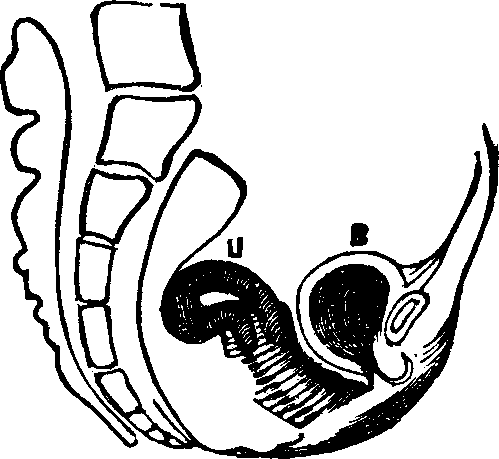

Fig. 10. Flexion, u, Uterus, B, Bladder.

Fig. 11. Version, u, Uterus, B, Bladder.

Flexions and Versions of the Womb. Flexion of the uterus, in which it is bent upon itself, as illustrated in Fig. 10, produces a bending of the cervical canal, constricting or obliterating it, and thus preventing the passage of spermatozoa through it. Version of the uterus [pg 710]in which its top, or fundus, falls either forward against the bladder (anteversion), as illustrated in Fig. 11, or backward against the rectum (retroversion), may close the mouth of the uterus by firmly pressing it against the wall of the vaginal canal, and thus prevent the passage of spermatozoa into the womb. 'The treatment of these several displacements will be considered hereafter. We may here remark, however, that they can be remedied by proper treatment. Our mechanical movements, manipulations, and kneadings are invaluable aids in correcting these displacements.